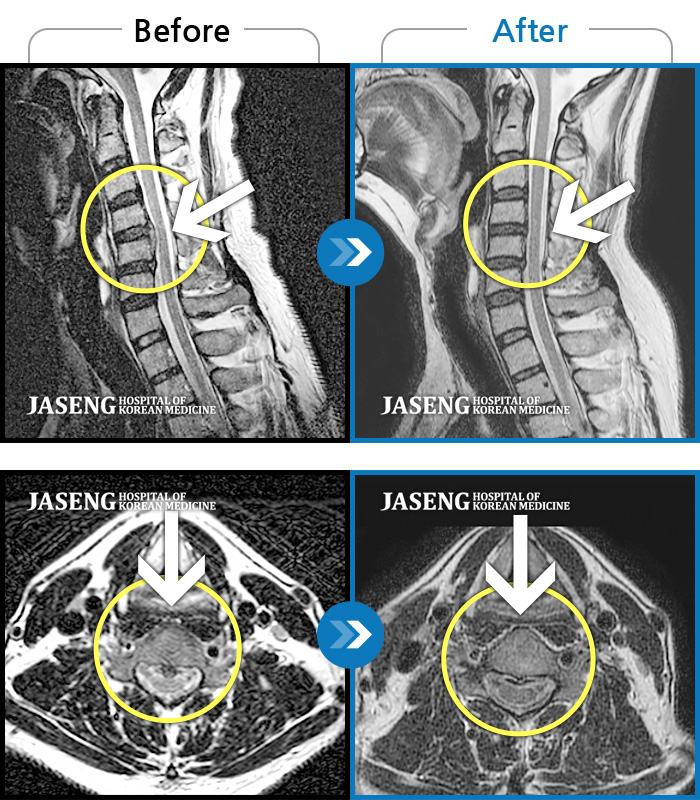

• 목디스크